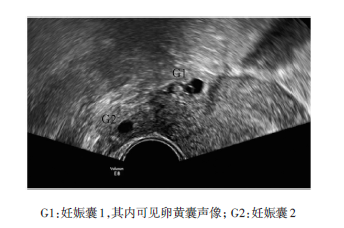

患者30岁。巳婚,G2P0,因停经42d,阴道不 规则流血13 d,下腹痛1 d,外院查血P-HCG 9638 U/L,超声提示“异位妊娠”可能,急诊转入我 院进一步诊治。查体:一般情况尚可,T36.5°C,P 92 次/min,R 20 次/min,BP 98/62mmHg,心肺正常, 肝脾未触及,右下腹压痛,无反跳痛,移动性浊音 (-),余无特殊。妇科检查:外阴发育正常,阴道通 畅,见少量鲜血,宫颈举痛及摇摆痛,右附件区增 厚,压痛。平素月经规律,末次月经2013-09-26, 自然受孕。2008年因异位妊娠在外院行“左侧输 卵管切除术”,余无特殊。超声检查显示:子宫稍 大,宫腔内未见明显妊娠囊声像,内膜厚1.8 cm,宫 腔分离0.8 cm。子宫右侧宫角处向外突出大小约1.4 cmX1.3 cm包块,与子宫内膜不相通,其内可见 大小约0.7 cmX0.6 cm妊娠囊,可见卵黄囊,未见胎 芽及胎心搏动。右附件区另探及大小约1.5 cmX1.1 cm包块,呈“Donut”征,其内可见大小约0.6 cmX0.5 cm无回声区,未见明显卵黄囊及胎芽声像 (图1)。双侧卵巢未见明显异常,直肠子宫陷凹探 及1.7 cm液性暗区,透声差。超声提示:右侧附件 区双妊娠囊双胎妊娠可能(右侧输卵管间质部合 并壶腹部妊娠)宫腔及盆腔少量积液。入院后完 善相关检查,积极补液,在全麻下行急诊剖腹探查 术+右侧输卵管间质部妊娠开窗取胎术+右侧输卵管壶腹部妊娠开窗取胎术+盆腔粘连松解术,术中 见腹腔有陈旧性血液约30 mL,左侧输卵管缺如, 右侧输卵管间质部及壶腹部可见膨大,表面紫蓝 色,无破口,输卵管伞部可见陈旧性血凝块,双侧 卵巢正常,完整挤出妊娠组织,局部注射甲氨蝶呤 50 mg,妊娠组织送病检,手术顺利。术后病理诊 断:右侧输卵管间质部、壶腹部见绒毛组织及滋养 叶细胞。患者术后第3天查血P-HCG 699.03 U/L, 术后第4天出院,出院后每周复查1次血P-HCG,2 周后血P-HCG降至正常范围,随访期间患者无并 发症发生。

本例患者孕前未使用过促排卵药物,为自然 受孕,5年前因左侧输卵管妊娠,切除左侧输卵管, 为异位妊娠的高发人群,停经后不规则阴道流血, 下腹痛,尿HCG( + ),有典型的临床症状,经阴道超 声检查宫腔内未探及妊娠囊声像,右侧附件区探 及2个独立的妊娠囊,提示右侧输卵管不同部位双 胎妊娠可能,并经手术证实。

本例患者就诊及时,右侧附件区2个独立的妊 娠囊均未破裂,阴道超声诊断明确。对于停经时 间较长,异位妊娠包块已破裂或流产时,超声不能 做出输卵管多胎妊娠的准确诊断,确诊有待于术 中探查及术后病理诊断。经阴道超声检查比经腹 部超声检查可以更早显示妊娠囊,当临床怀疑异 位妊娠,腹部超声检查宫腔内未探及妊娠囊时,应 进一步行经阴道超声检查,检查过程中应对子宫 及双附件区详细检查,对异位妊娠高发人群,超声 医生要注意宫内外同时妊娠、同侧或双侧输卵管 双胎妊娠等特殊异位妊娠的可能,尽量做到早期 准确诊断,减少误诊、漏诊,为临床诊疗提供更为 准确的辅助信息。